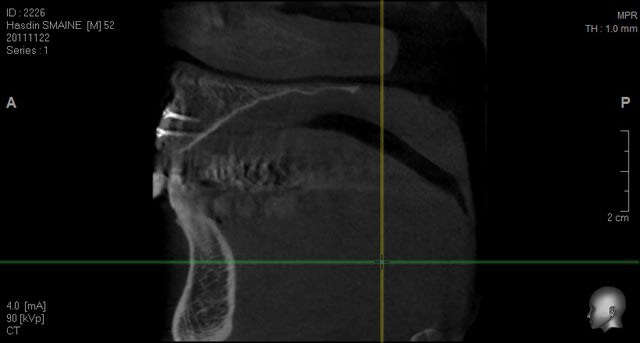

Oui, c'est très simple.

Et mon avis est difficilement objectif maintenant que j'ai l'appareil, mais la qualité est excellente...

voilà des images de tout les jours....